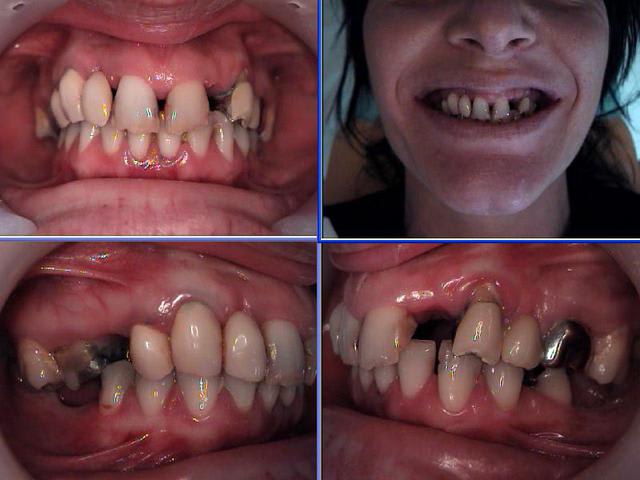

Céramik comme promis Ma réponse en image 2ans après

Est ce l'échec affirmé par certains?

1 Pano du cas

2 Pano qui a déclenché tous ces gentils commentaires

5 Pano aujourd'hui (le secteur 4 fichu???)

Vos avis!

Finalement : la paro en secteur 4 : pas mal, pour des dents que beaucoup voulait extraire.